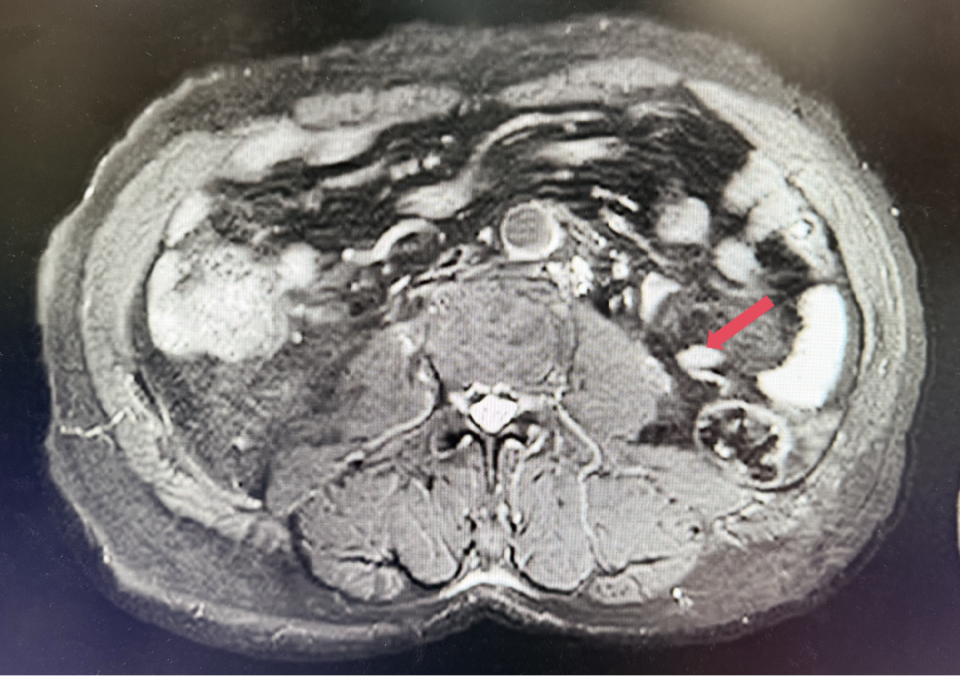

2023年11月,最深应答

2023年11月:治疗10个月(C15)评估,肿瘤负荷减少至41mm,维持PR。